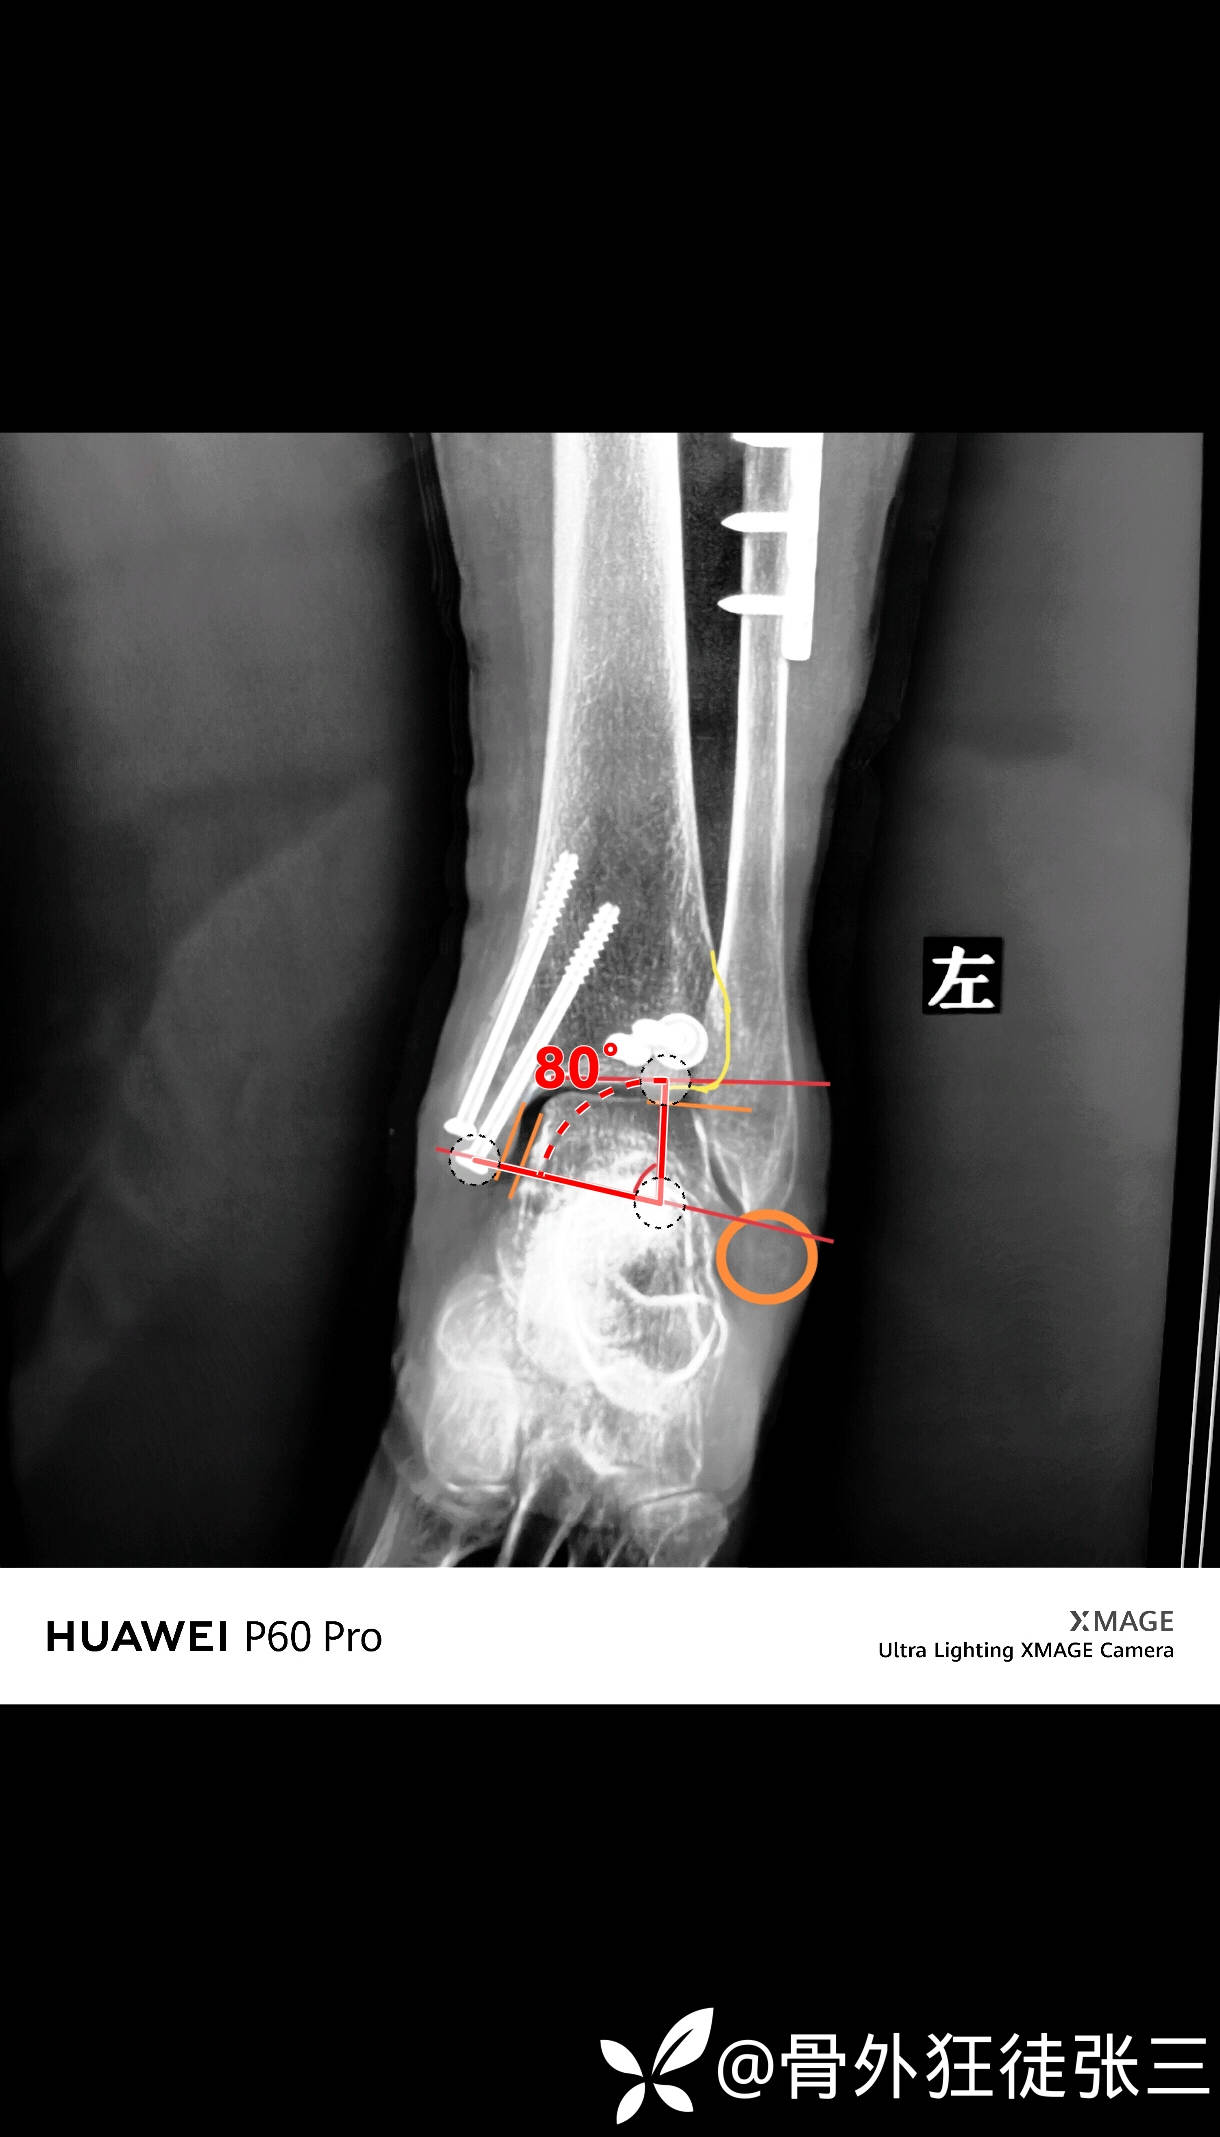

治疗经过:

1,侧卧位,腓骨切开复位

腓骨粉碎,三个游离骨块

只有前侧皮质复位标志,后侧,内侧,外侧,都是粉碎

钢板桥接后,碎骨块拼接

nice结捆扎与钢板

透视见腓骨长度恢复,复位良好

2,后外侧切口,复位后踝

透视见关节复位,骨折复位

两枚空心钉固定

内踝处有一个挫伤创面

经皮空心钉

没有再切口

术后CT验证

后踝骨折复位良好

下胫腓位置良好

内踝骨折位置良好。

内踝经皮空心钉小切口不明显

腓骨切口,后踝切口

LBD超减张缝合